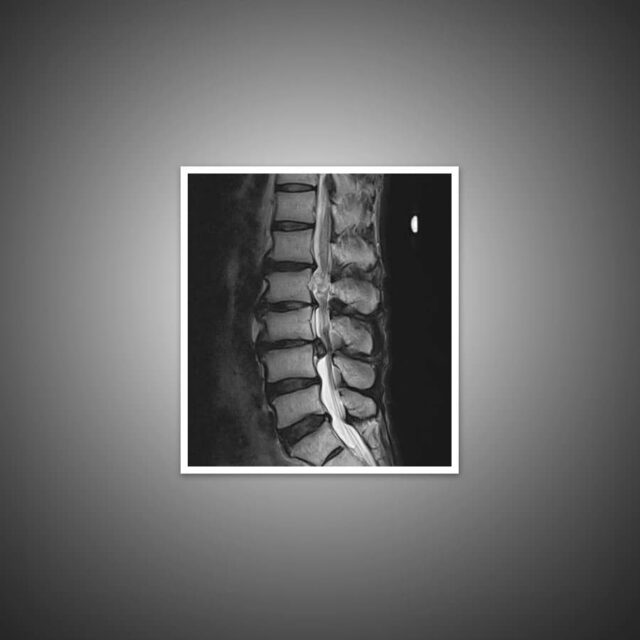

Can You Be Born With Degenerative Disc Disease . Degenerative disk disease occurs when the cushioning in your spine begins to wear away. Each disc has a gelatinous center and a tougher outer covering. Degenerative disc disease is a condition characterized by the gradual deterioration of the discs that act as cushions between the vertebrae in the spine. To comprehend the stages of ddd,. The condition is most common in older adults. Common symptoms of degenerative disc disease. Degenerative disc disease is a condition that affects the discs between the vertebrae in your spine. While some patients with degenerative disc disease are asymptomatic, others develop severe, persistent back or neck pain. Whether you’re currently struggling with degenerative disc disease or simply want to be proactive about preventing it, this article offers.